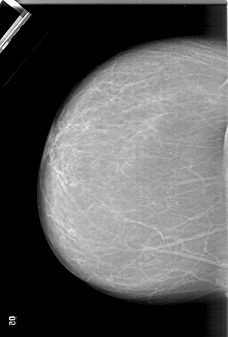

A_1333_1.RIGHT_CC

LEFT_CC LINES 6391 PIXELS_PER_LINE 4321 BITS_PER_PIXEL 12 RESOLUTION 43.5 NON_OVERLAY